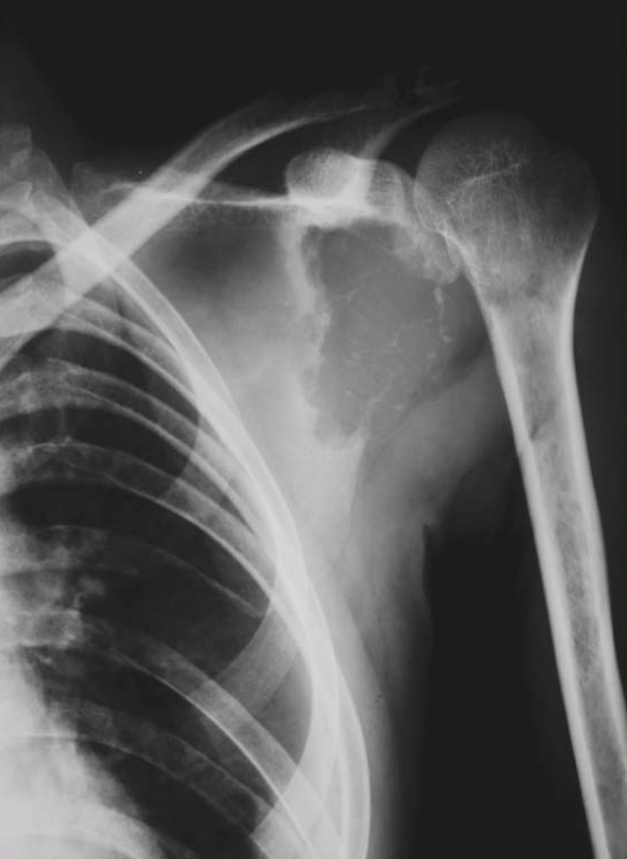

Figure3